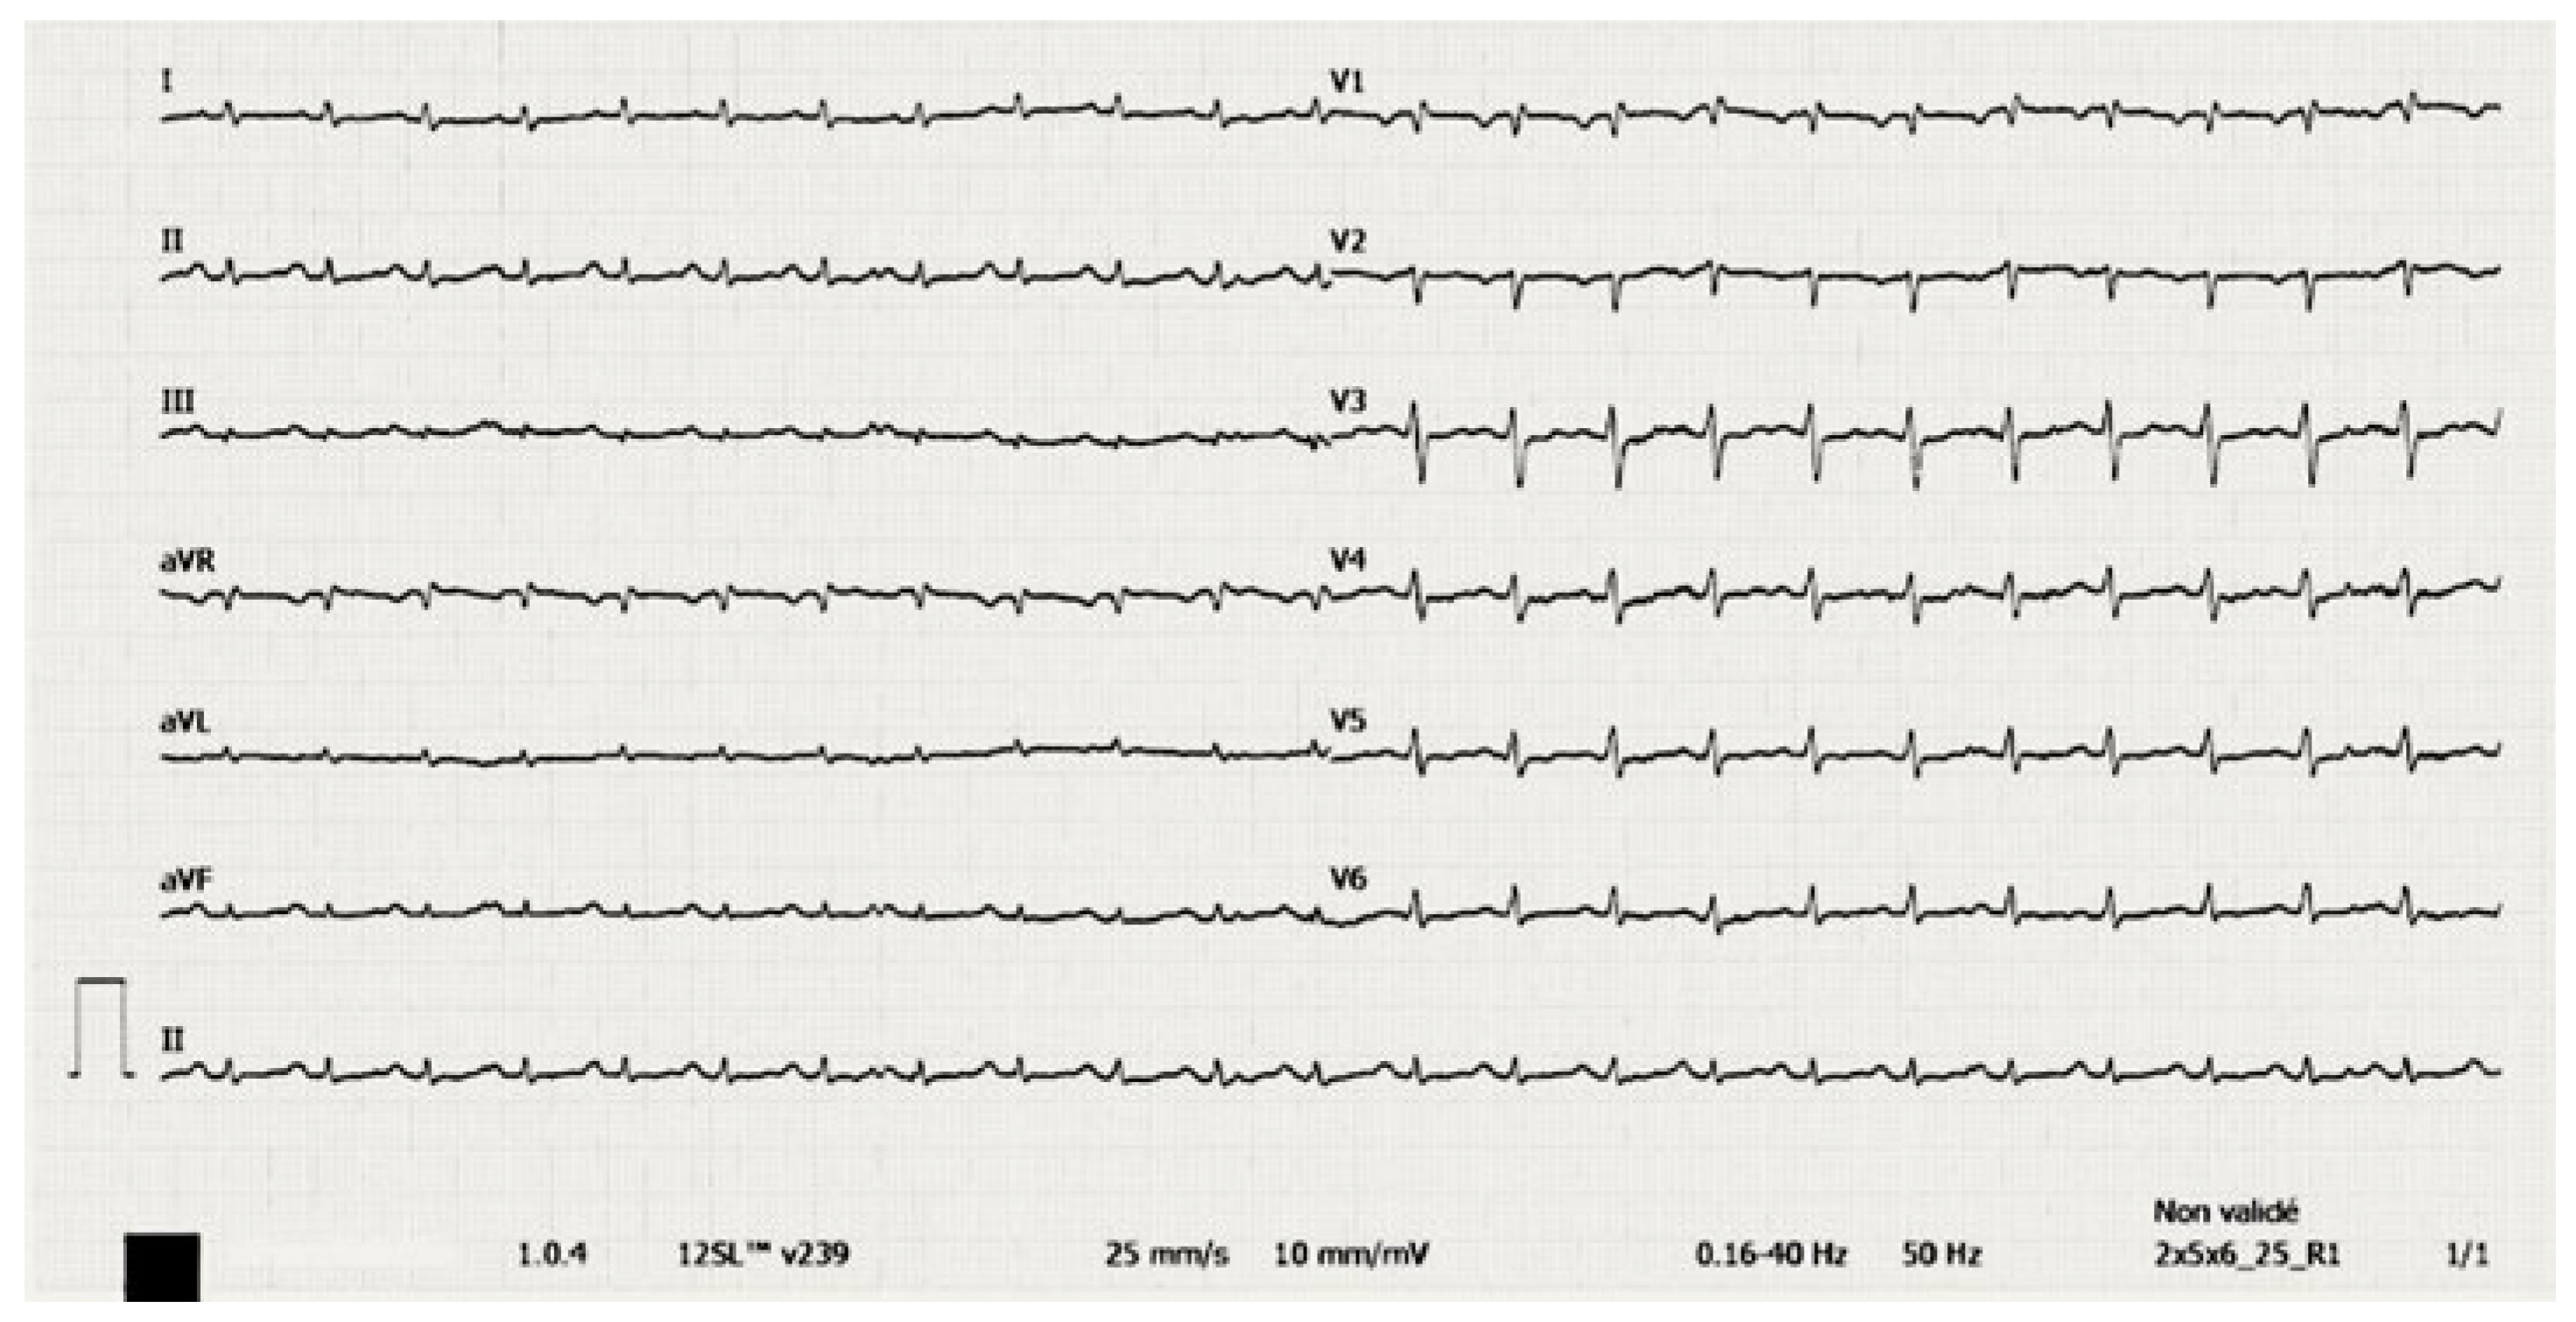

Relapsing Terlipressin-Induced Acute Pulmonary Oedema in a Patient with Hepatorenal Syndrome

Case description